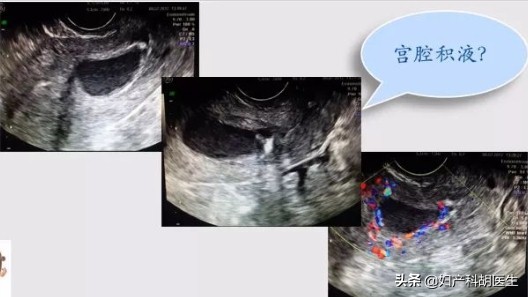

什么是宫腔积液?

宫腔积液,顾名思义,就是是指子宫腔内有液体积聚,那么积聚的液体就可能是积水、积血或者积脓。有宫腔积液不代表一定是生病了,可能是生理性的,也可能性是病理性的。

病人是一个农村老年女性,58岁,绝经5年,从未定期妇科检查。这次因为村里妇科普查时B超发现宫腔积液,居委会再三嘱咐后她才来医院。复查B超后仍然提示宫腔积液,前后径约5 mm,透声差,内膜厚5mm,子宫略增大,双侧卵巢未见明显异常。